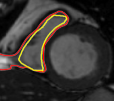

The problem above is a generalization of Horn & Schunck optical flow. Note that solving for the Horn & Schunck optical flow within each region separately does not lead to motions such that at the interface, they have equal normal components (see Figure 1), whereas the solution of (5) to be presented in subsequent sections does. Note that computing Horn & Schunck optical flow in each region requires boundary conditions (and typically they are chosen to be Neumann boundary conditions: and on ). Note that replacing these boundary conditions with the boundary constraint (6) does not specify a unique solution. Also, while Horn & Schunck optical flow computed on the whole domain naturally gives a globally smooth motion, which by default satisfies matching normals at the interface, this is not natural for the ventricles / myocardium, where different motions exist in the regions (see Figure 2), and the motions should not be smoothed across the regions.

![]() |

| image + boundary | next image | within region optical flow | our method |